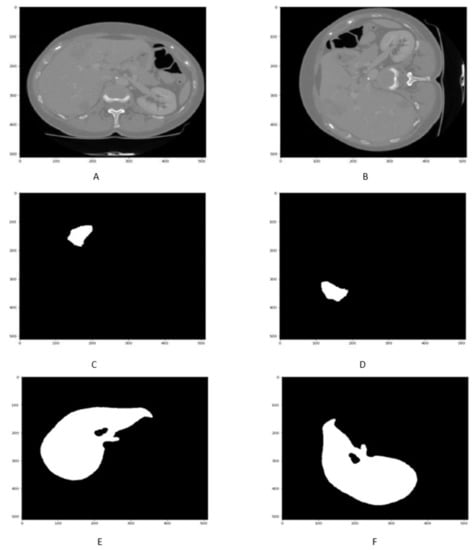

4.3. Tumor Segmentation Results

The qualitative and quantitative result of liver Tumor CT scan segmentation is shown in Figure 8 and in Table 3. The proposed technique has been obtained in terms of liver segmentation as assessed by DSC, accuracy, precision, specificity VOE, and RVD values. The Figure 8A,B and Table 3 highlight the better performance of proposed approach.

Figure 8.

Figure shows that the samples of Liver Tumor segmentation in (A,B).